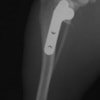

術後側面像

半年にわたる左後肢の跛行が認められるとのことで来院されました。触診にて左膝関節の疼痛、内側部の腫脹、膝蓋骨の内方脱臼を認めました。レントゲン検査にてfat pad signを伴う関節炎が認められたことから、前十字靭帯断裂と膝蓋骨内方脱臼( GradeⅢ)の併発と診断し、手術を行いました。術中の関節鏡検査にて前十字靭帯の完全断裂を確認、関節液検査にて感染を除外した後、TPLOと、滑車溝形成を始めとした膝蓋骨脱臼整復術を実施いたしました。

術前側面像

術前に25°であったTPAは、TPLO実施により7°に矯正されました。症例の歩行状態は良好です。